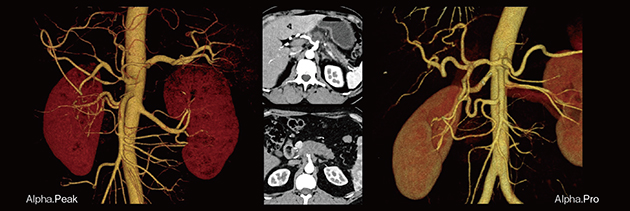

PCD-CTは,特に膵がんの血管解剖や腫瘍の境界の描出に最適である(図6)。微小血管を描出できるため,肝胆膵切除術の術前計画における有用性が高い。

図6 高解像度画像による膵がんの血管解剖および腫瘍境界の描出

当院で稼働するPCD-CTは,Dual Sourceで検出器が6cmの「NAEOTOM Alpha.Peak」,Dual Sourceで検出器が4cmの「NAEOTOM Alpha.Pro」,Single Sourceの「NAEOTOM Alpha.Prime」の3機種である。

NAEOTOM Alpha.Proは,救急部門のバックアップとして,集中治療患者や血管および心臓の診断,内科や整形外科の入院患者,インターベンションなどに使用している。